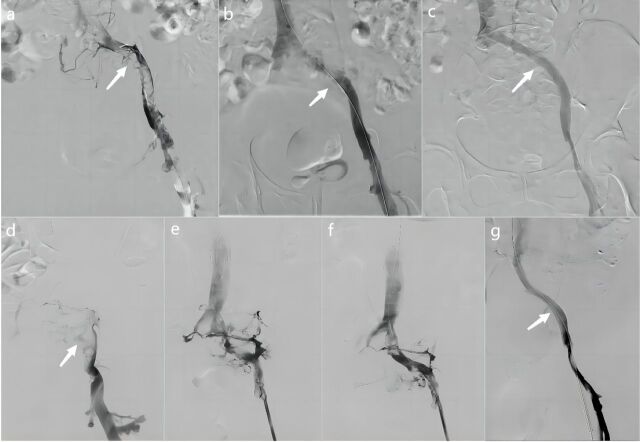

Objectives: To assess the clinical outcomes and prognoses of various stent implantation timings after percutaneous mechanical thrombectomy (PMT) in patients with iliac vein compression syndrome (IVCS) complicated by acute iliofemoral deep vein thrombosis (IFDVT).

Methods: A total of 99 patients diagnosed with IVCS with acute IFDVT from December 2016 to February 2024 at our institution were retrospectively analyzed. Patients were divided into 2 groups: Group A underwent simultaneous iliac vein stent implantation, while Group B received staged stent implantation after local urokinase thrombolysis. The 2 groups were compared on the basis of limb edema resolution within 3 days postsurgery, urokinase doses, hospitalization duration, and in-stent patency during follow-up.

Results: During the follow-up, the stent occlusion rates were comparable between the 2 groups. Compared with Group B, Group A experienced faster limb edema resolution within 3 days postsurgery and required lower urokinase doses and a shorter hospitalization duration. In Group B, 13 patients needed additional stent implantation due to iliac vein occlusion after thrombolysis.

Conclusion: Simultaneous iliac vein stent implantation, as opposed to staged placement after PMT, improved limb edema resolution within 3 days, reduced urokinase doses, and shortened hospital stays.